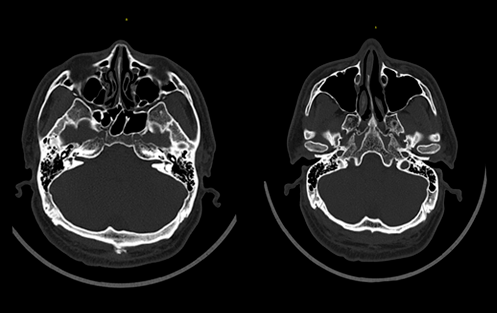

臨床圖像